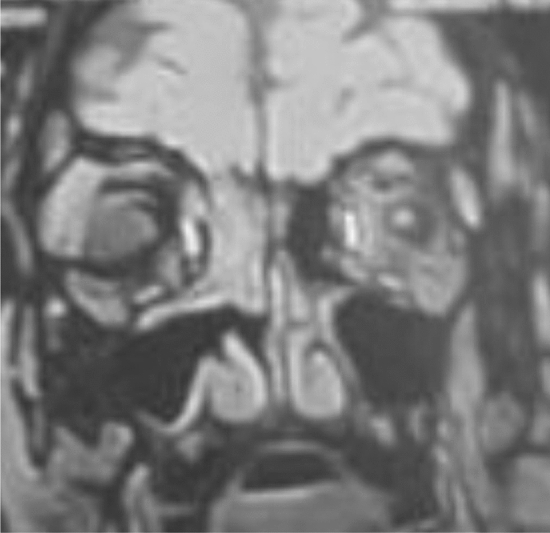

Specific case scenarios of the enrolled patients (Figs. 3 and 4)

A male patient presented with bilateral rhino-fascial -cerebral CAM.

Case (2) Male patient 62 y old; from Assiut; Egypt; heavy smoker; uncontrolled D.M., CKD grade 4 (estimated G.F.R. = 13.9 ml/min/1.73 m2); presented by bilateral rhino-facial mucormycosis and bilateral 1st;3rd,4th and 6th C.N. palsy. Diagnosed COVID-19 (by C.T. chest and PCR) during preparation for E.N.T. (Ear, Nose, and Throat) intervention. Brain M.R.I. M.R.A. C.T. sinuses with biopsy and histopathology were done to confirm the diagnosis of rhino orbital cerebral black fungus complicated by right cavernous sinus thrombosis and complete internal carotid artery occlusion. The patient showed rapid deterioration with sepsis and multi-organ failure and died (Fig. 4).